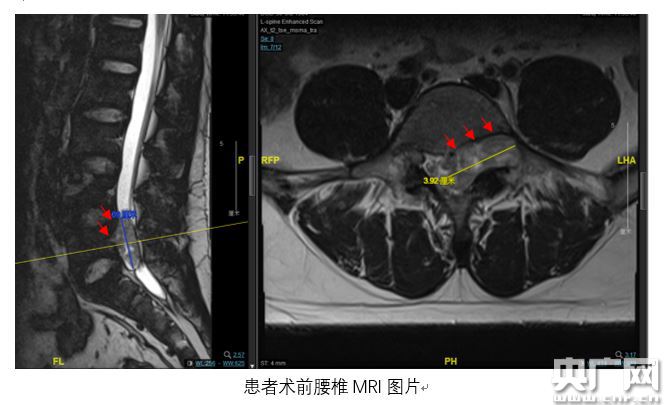

腰椎MRI檢查結(jié)果顯示,小陳腰骶部椎管內(nèi)有一個呈啞鈴型異常占位,占據(jù)了左側(cè)椎間孔且破壞到椎體骨質(zhì),憑借豐富臨床經(jīng)驗(yàn),趙杰主任診斷意見為椎管內(nèi)神經(jīng)鞘瘤,需盡快手術(shù)。